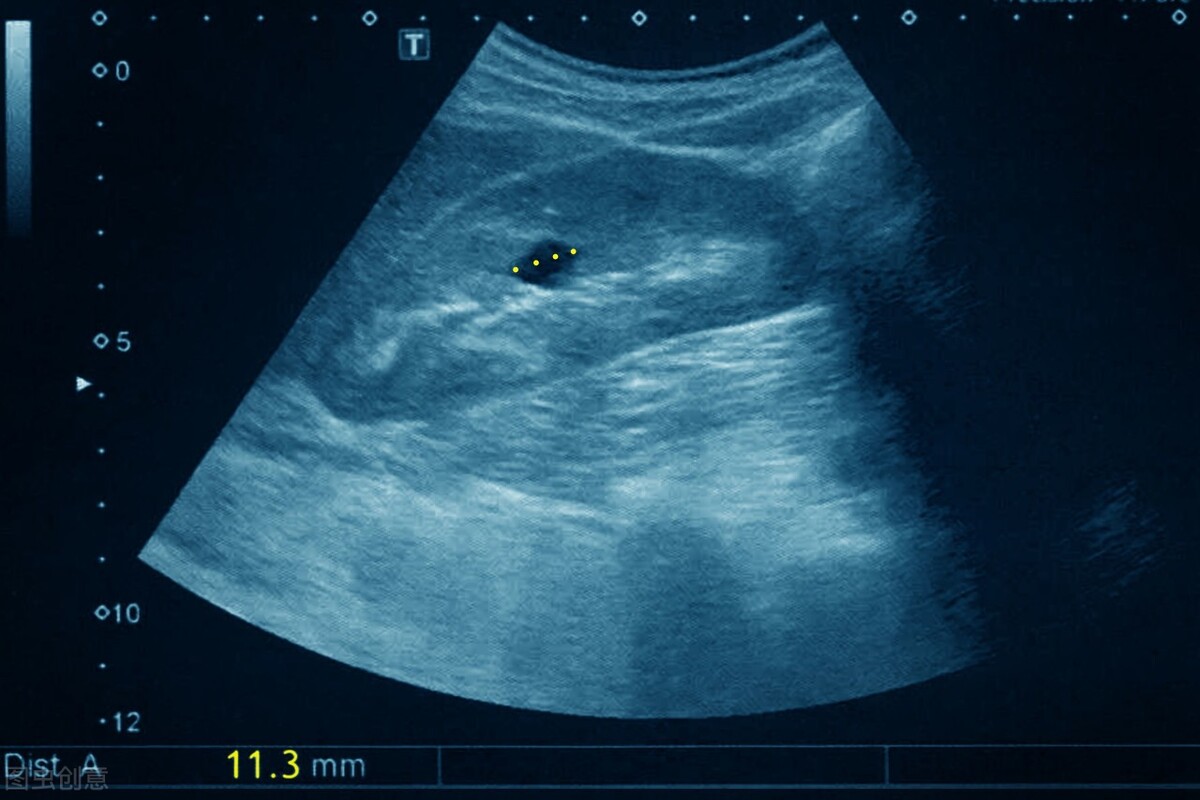

查房的时候,一名住院患者问我。我接过B超单看了一下,在患者右肾中极有一个直径不到2公分的小囊肿。我告诉他:肾脏囊肿在中老年人身上特别容易出现,是一种良性的病变,不要过分担心。一般直径大于4厘米,或者有明显症状时,才会考虑手术治疗。

肾囊肿